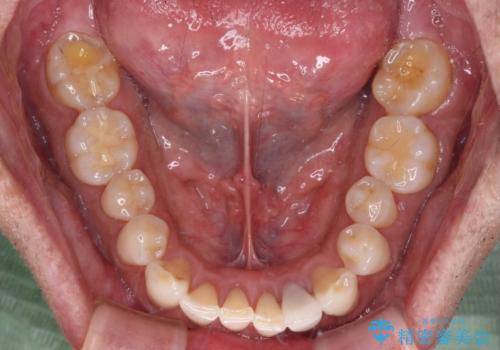

内側にある歯が干渉する 上顎前歯の部分矯正

- 上顎の前歯が内側にあり、下顎のセラミッククラウンと干渉することが気になるとのことで来院された患者様です。

上顎前歯にワイヤー装置を装着し、セラミッククラウンとは干渉しないようにしながら歯列を整えることとしました。

セラミッククラウンとの干渉はすぐに改善され、歯列も整いましたが、一方で、前歯で食事が噛みにくくなり、1年近い治療期間となりました。